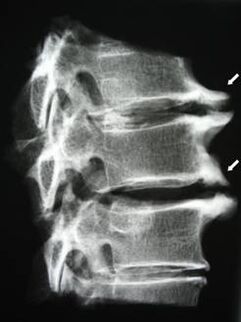

Սկզբնական փուլերում օստեոխոնդրոզը հայտնաբերվում է MRI-ի միջոցով. Հետագայում պաթոլոգիան կարող է ախտորոշվել ռադիոգրաֆիայի միջոցով: Արգանդի վզիկի ողնաշարի ռադիոգրաֆիաներում նկատելի են դառնում ողնաշարերի միջև հեռավորության նվազում, ֆասետային հոդերի պաթոլոգիական փոփոխություններ և օստեոֆիտոզ:

Արգանդի վզիկի ողնաշարի օստեոֆիտները պարանոցի ցավ են առաջացնում